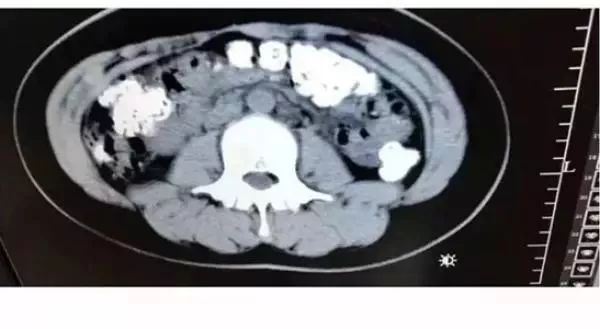

CT检查发现

胃肠道布满一颗颗圆圆的高密度阴影

——没有消化的“珍珠”。

接诊医生张楼炜见她肚子鼓鼓的,便安排了腹部CT,检查结果让他一惊:患者胃部、横结肠、升结肠、降结肠、乙状结肠,一直到肛门,全是颗粒状阴影,足有百余颗。